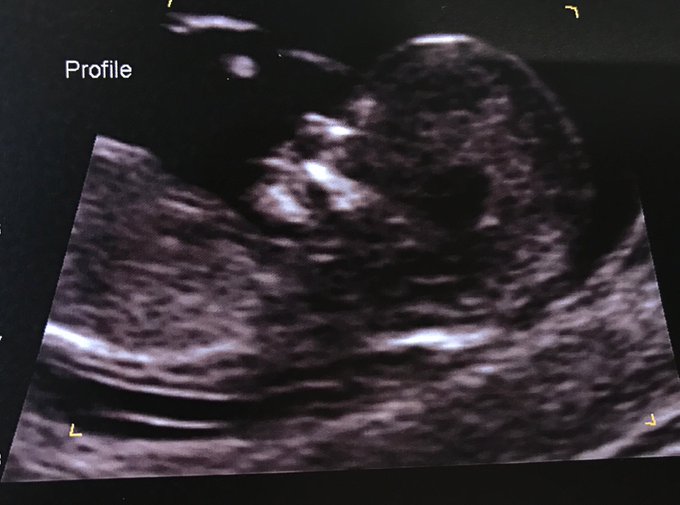

Finalmente, y luego de las graciosas especulaciones de los usuarios, Sharni publicó una fotografía más amigable del pequeño. "Afortunadamente es mucho más lindo de lado", afirmó.